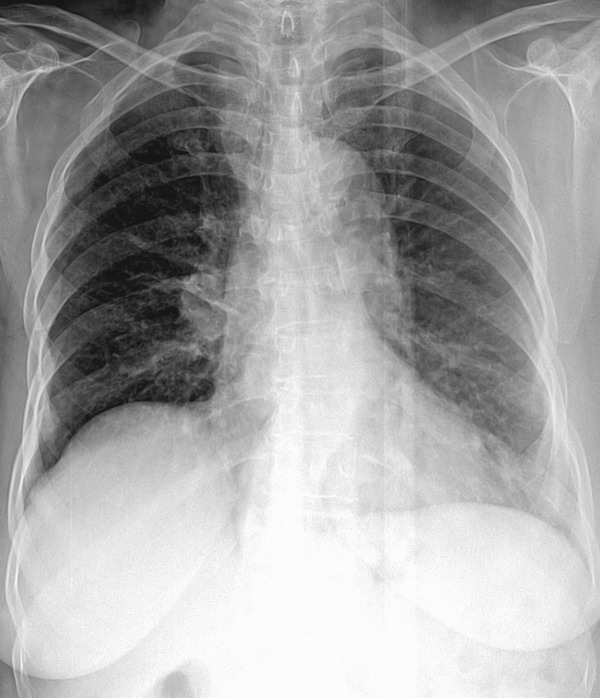

m 77y 喘 气短6个月

右肺门区见一团块状略高密度影,边缘尚清,右中下野内带区见略高密度影,质尚均,余所见右肺野密度普遍减低,肋间隙增宽;右膈局限性隆起;纵隔影增宽。

考虑右肺门区占位性病变伴局限性肺不张;右上肺代偿性气肿;建议ct或进一步检查。

右肺中心型肺癌伴肺不张可能性大-----右肺门肿块,气管纵隔右移,右侧膈肌抬高

右肺门中央性肺癌伴右上肺节段性不张。右膈面抬高。

右肺门肿块,气管纵隔右移,右侧膈肌抬高.

右肺门影增大,右侧膈肌高位,没有肺不张,建议透视观察,有无膈肌矛盾运动,除外膈神经麻痹